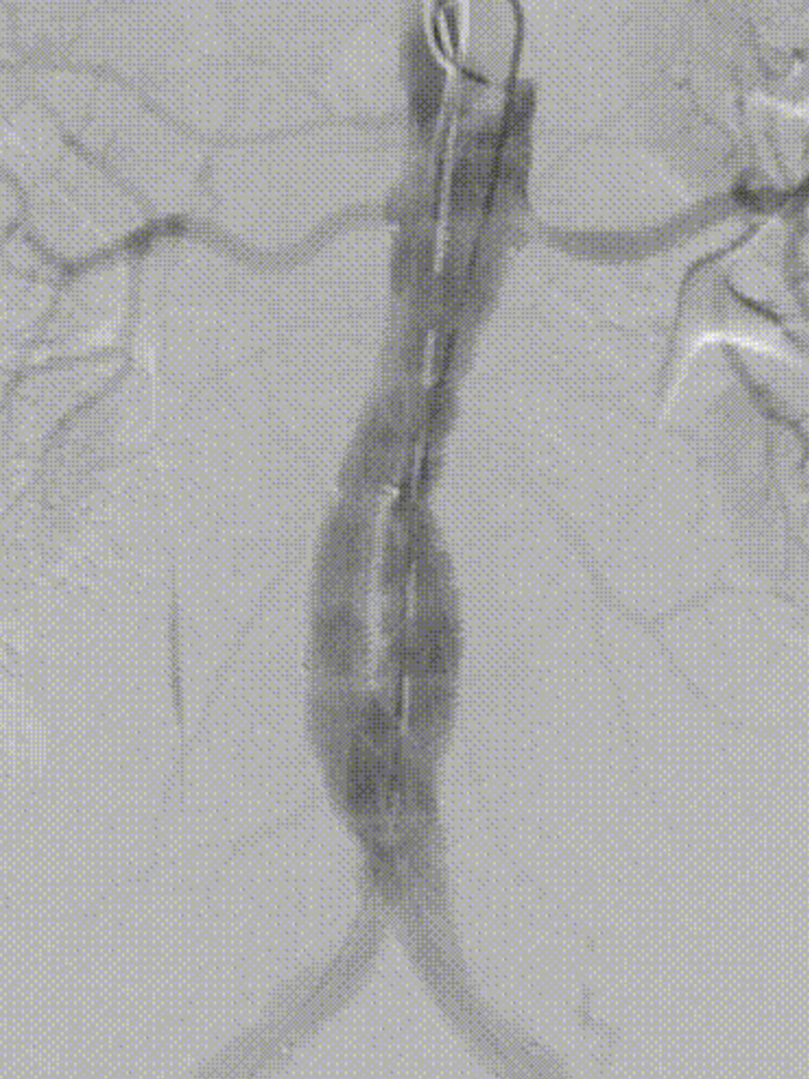

理想瘤颈和合适OVERSIZE的重要性

理想的瘤颈加上合适的OVERSIZE可以使垂直作用力和水平摩擦力恰到好处,形成紧密均衡的贴合。

这种状态下的支架依靠垂直作用力和水平摩擦力牢固定位,不需要依赖后释放挂钩固定。

短瘤颈和梯形瘤颈的处理方法

短瘤颈可以先打开后释放提前定位,这样能相对保持定位准确。

短梯形瘤颈可通过PUSH UP减少支架与血管壁之间空余,促进贴合,增加两力充分作用;并建议适当增大OVERSIZE、先打开后释放做定位保障。